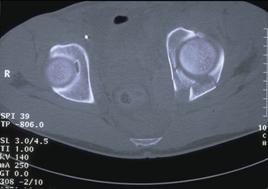

Fractura Malgaigne Fractura Malgaigne. Imagine CT

Fractura de

aripa iliaca stanga Fractura de aripa iliaca

stanga

Disjunctie sacro-iliaca stanga Disjunctie

sacro-iliaca stanga Aspect CT